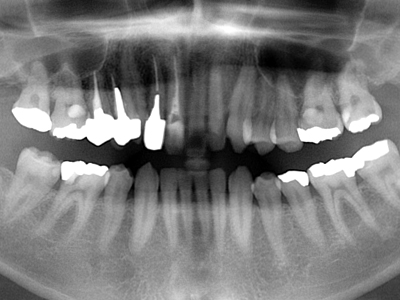

全顎パノラマ写真においては右上1番が失活歯、2番は叢生のままで不適合な前装冠(差し歯)、八重歯の3番は健全歯、4,5番も2番同様不適合冠処置となっています。比較的プラークコントロール(以下PCR)の良好な(歯ブラシの仕方が上手な)この患者様も同部が上手に磨けず不潔となり崩壊過程にあることが考えられます。

3. 初診時上顎